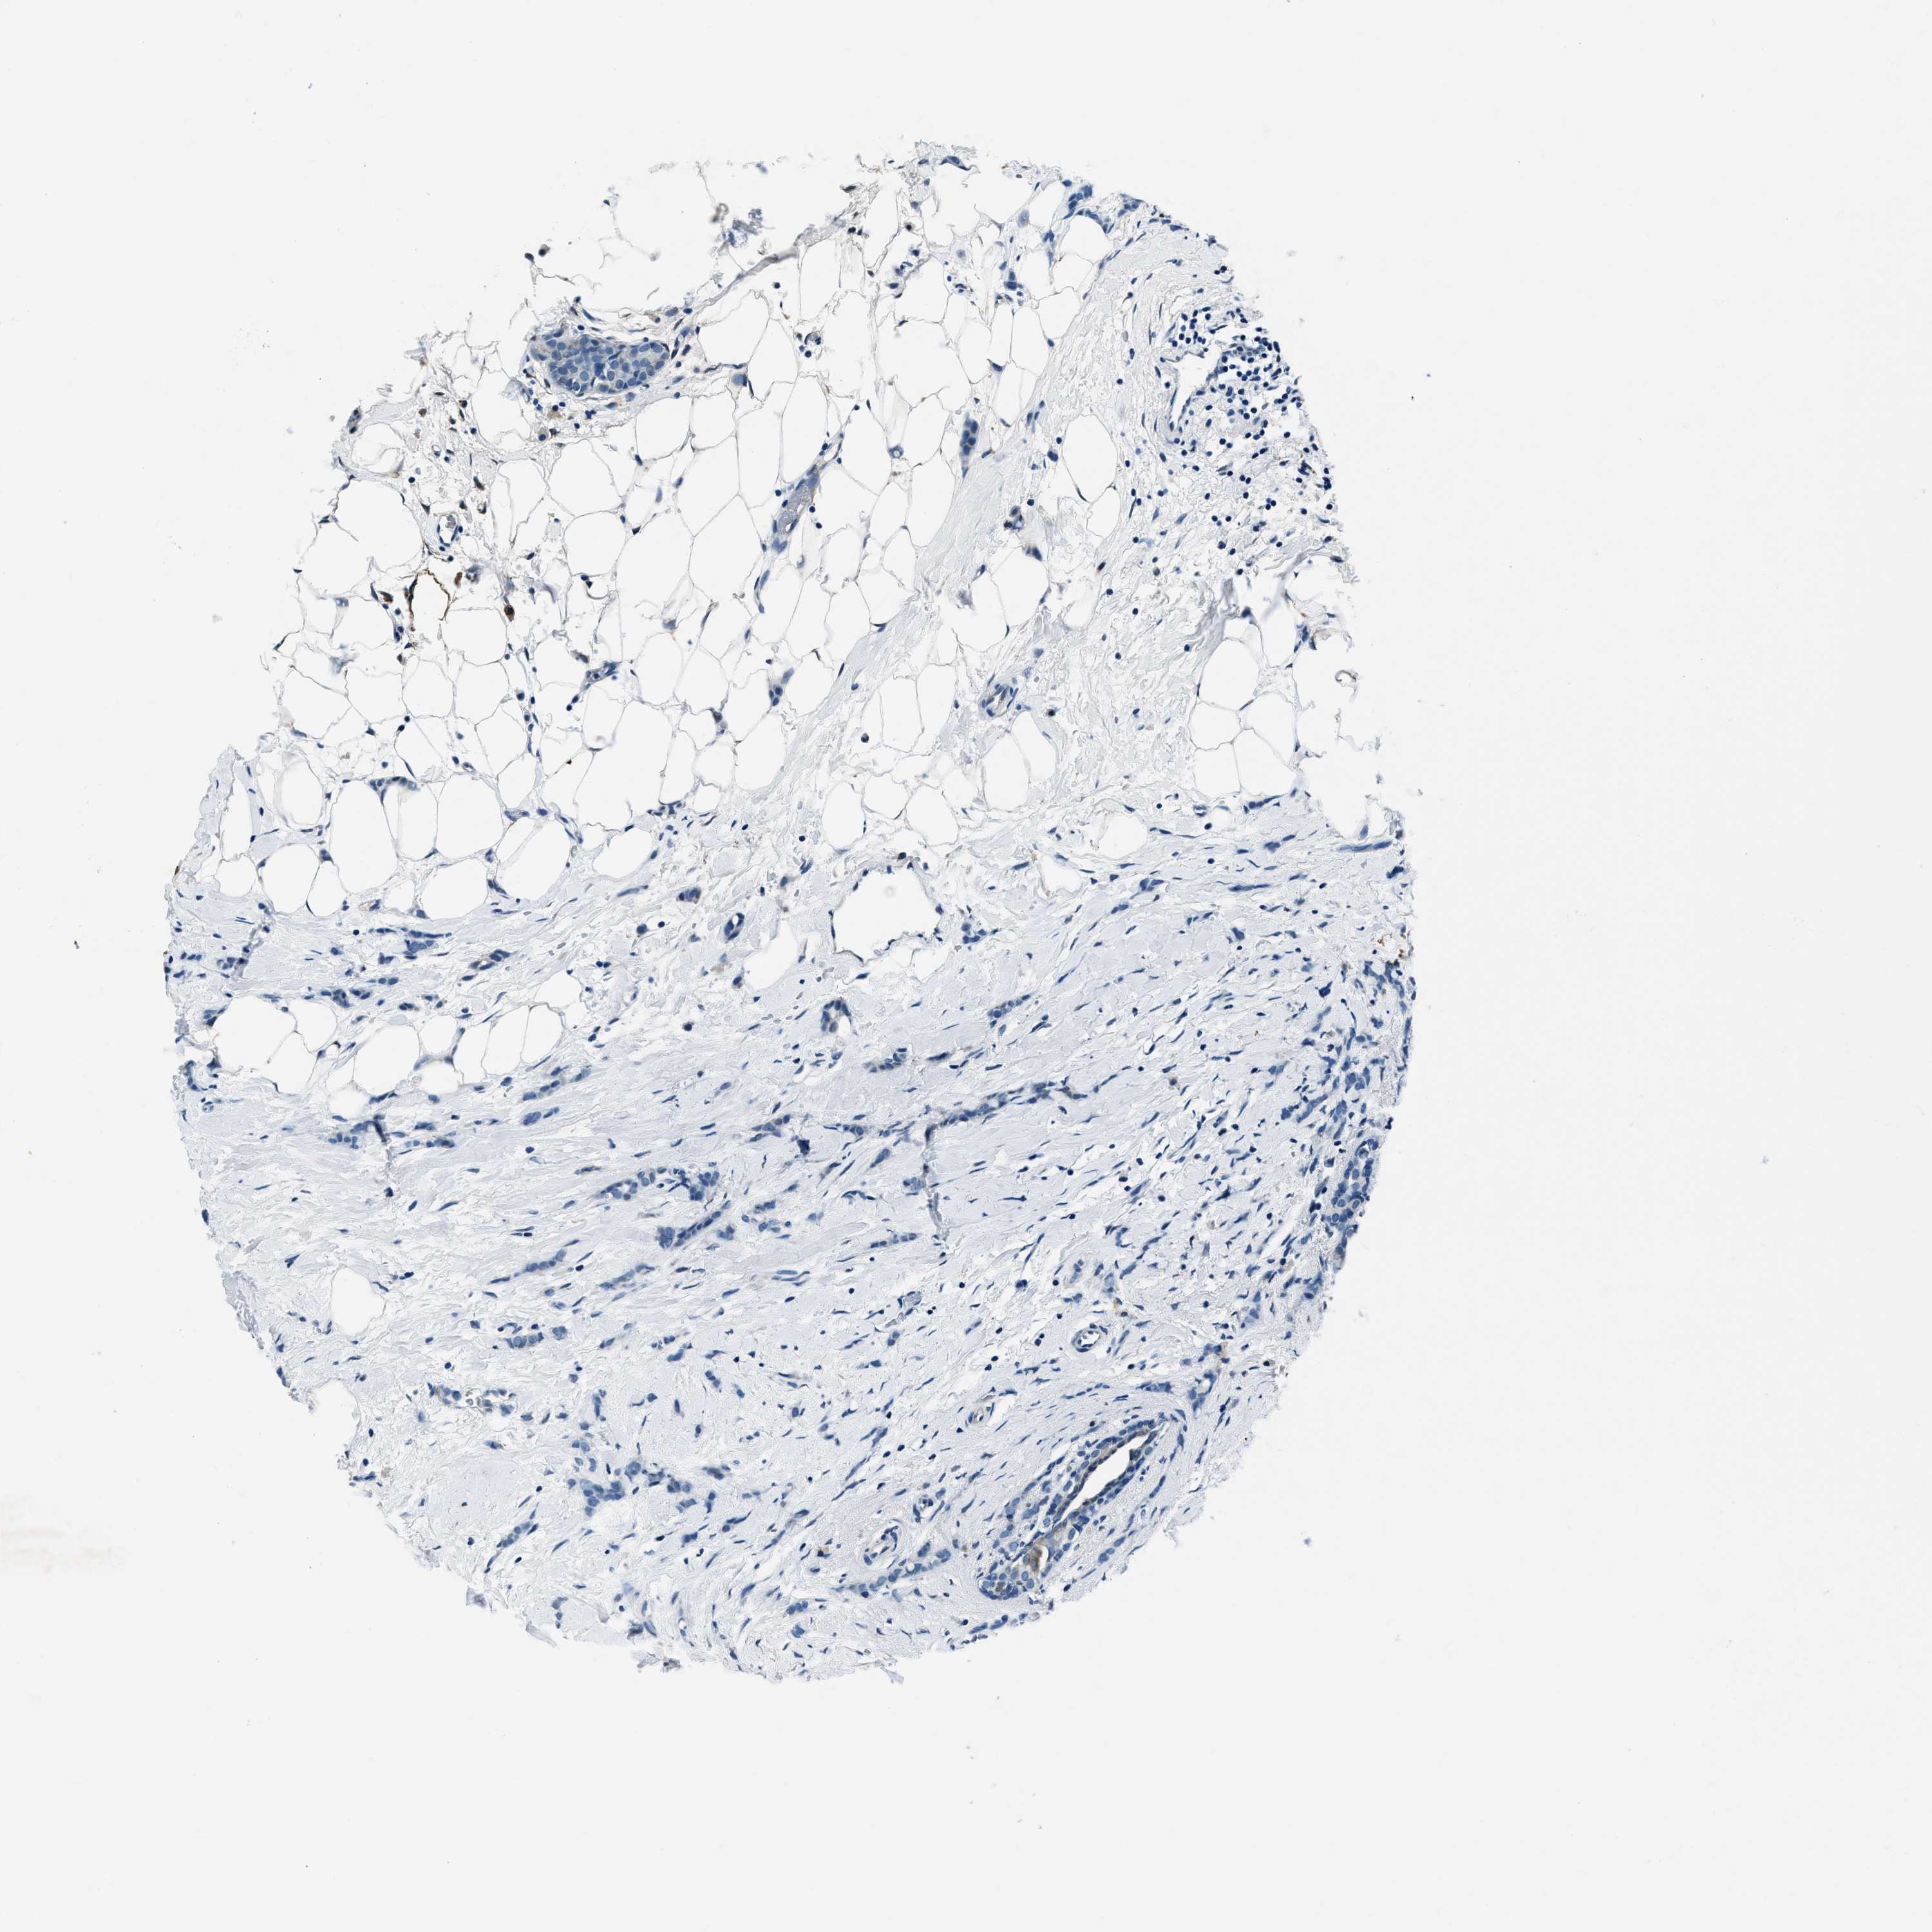

BRCA TCGA BRCA VALIDATION PROTEIN EXPRESSION